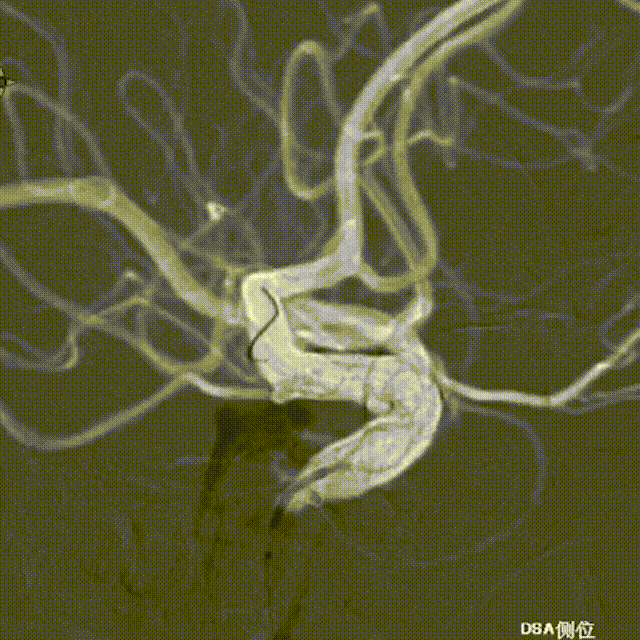

Tubridge Plus Case 1